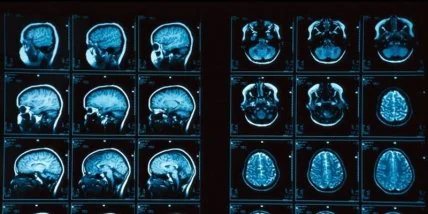

Найдено связующее звено между интеллектом и толщиной коры головного мозга.

Обнаруженный ген может объяснить затруднения, которые люди испытывают в процессе учебы, а также помочь в излечении многих болезней. Международная группа ученых проанализировала образцы ДНК и результаты сканирования мозга более чем 1500 подростков, а также провела серию тестов для определения коэффициента их вербального и невербального интеллекта.

Ученых интересовала, в первую очередь, толщина коры головного мозга испытуемых, так называемой ''серой материи'', которая играет ключевую роль в развитии памяти, уровня внимания и восприятия, мышления и совести. Затем были проанализированы десятки тысяч (более 54 000) генетических вариантов, которые могли оказать влияние на процесс развития мозга. При этом удалось доказать, что у подростков с определенными генами кора в левом полушарии головного мозга была тоньше. Именно они показали наихудшие результаты в тестах IQ.